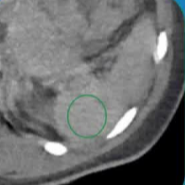

弹簧栓子的位置:胰大动脉和胰背动脉之间

|

白色细箭头:胰背动脉

白色粗箭头:胰横动脉

短黑箭头:血液流动方向

※:弹簧栓子 |